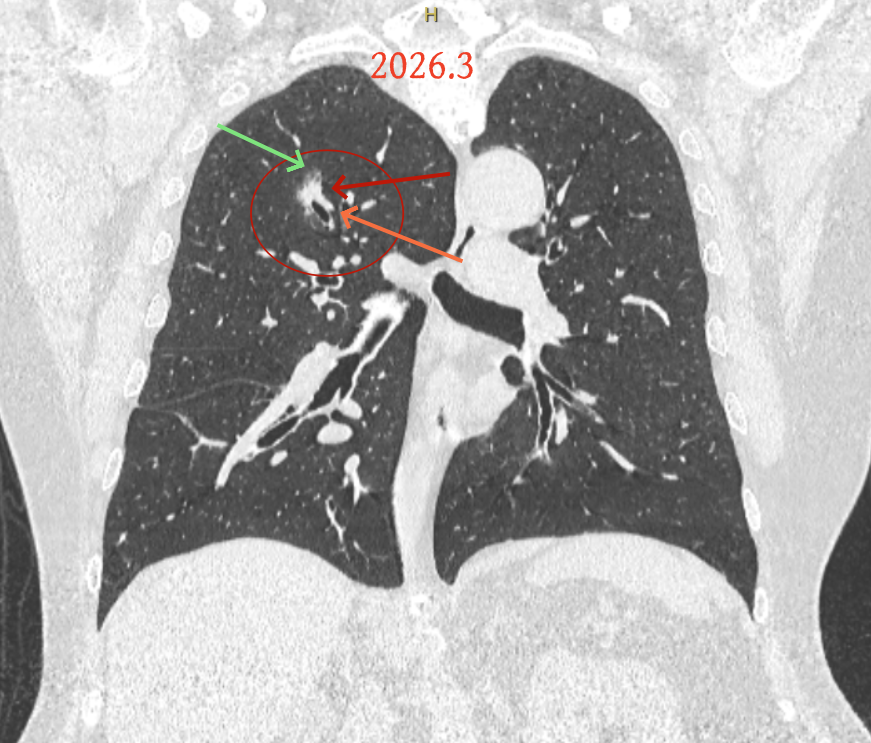

第三次问诊:2026.3

影像展示与分析:

但病灶B却显然进展!变成以实性成分为主的了!

再看2026年3月最近复查时不同层面病灶A的细节影像特征:

微小血管走向病灶,磨玻璃的密度淡而较纯。

再看病灶B的2026年3月细节影像特征:

边缘位置也是较淡的磨玻璃成分。

上图是混合密度,轮廓较清,瘤肺边界欠清晰。

病灶A以及他处磨玻璃结节其实进展都是不明显的,略与2022年比,病灶A稍显明显点。病灶B开始时极淡,之前进展虽有但也甚微,直到2025年9月仍是磨玻璃成分为主,只是点状少许密度稍高成分。但在最近半年内却显然进展!若从影像上判断,基本上就得是浸润性腺癌了。那有几点:一是必不能再随访;二是大小来看仍是1A期;三是从快速进展来说,可能含有部分高危亚型,比如微乳头或实体型等;四是他处的磨玻璃结节以及病灶A显然不能用病灶B的转移来解释,仍考虑是多原发早期肺癌。

结友问能否先穿刺?我是这么考虑的:你这个病灶B一是位置深,且靠近附近的血管,不容易穿刺;二是从影像变化来看,基本上肯定是恶性的,不是100%,也是95%以上的概率。刚才我又在重建看冠状位与矢状位以及各次影像,目前混合密度的其实是后来者居上,原来刚开始是它比旁边的病灶密度淡的,但它的密度不是太纯,前次你自己也说似乎有点状偏实性成分。只是最近这半年进展特别快。这说明它的恶性程度较它边上原来就比较明显的那处恶性程度高,亚型中大概率有低分化的成分。所以从目前的影像来看,要尽快手术,而且切肺叶更为稳妥些。

这是较为少见的一个病例,磨玻璃为主,而且一直瘤肺边界欠清晰的病灶何以会在之前三年均极缓慢微小变化的情况下,近半年却快速进展呢?从影像细节上看,我们能否进一步分析哪种纯磨玻璃结节可能会较快进展?结合本例,我个人的考虑是:1、病灶整体显得是磨玻璃密度,但灶内并不均匀,就如磨玻璃密度中混入细沙状;2、整体轮廓虽然较清但瘤肺边界相对来说却并不太清晰;3、邻近有血管紧挨,而且与病灶这间缺乏间隙;4、病灶密度不高,没有明显实性成分,却有灶内有细支气管通气征,说明肿瘤成分具有收缩力,却与纯磨的收缩不匹配(纯磨一般不太会有明显收缩力)。如果有上面这些特征可能要提高警惕,一是适当较短的随访间隔,二是影像细节变化要更加注意,开始变化意味着已经进入发展期,而非蛰伏期。当然是否在2025年9月时定得手术了?如果是孤立性的病灶B,且位置位于能简单楔形切除的位置,那是可以考虑的。但位置深、两肺多发,切除范围不小,再今年据肺癌诊疗指南中说的混合磨玻璃结节实性成分不足25%是非侵袭性病变,且几乎不会转移,那么按原则仍再随访显然是可以的。本例的随访变化再次表明磨玻璃密度肺癌的诊疗个体化之路仍是很漫长的,按指南原则的随访或诊疗显然不足以覆盖所有病例,总结与经验积累永远在路上。